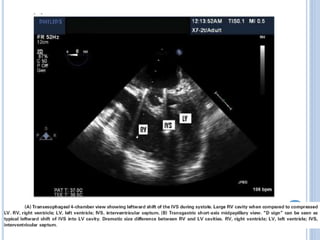

 Desplazamieno del septum IV (interdependencia

interventricular)

VENTRÍCULO DERECHO  VD dilatadoafecta el annulus de la válvula tricuspidea = insuficiencia  Exacerbación del estado de volumen del VD  Falla del VD  Desplazamieno del septum IV (interdependencia interventricular)  <volumen de fin de diástole VI= Falla cardiaca=perfusión tisular inadecuada